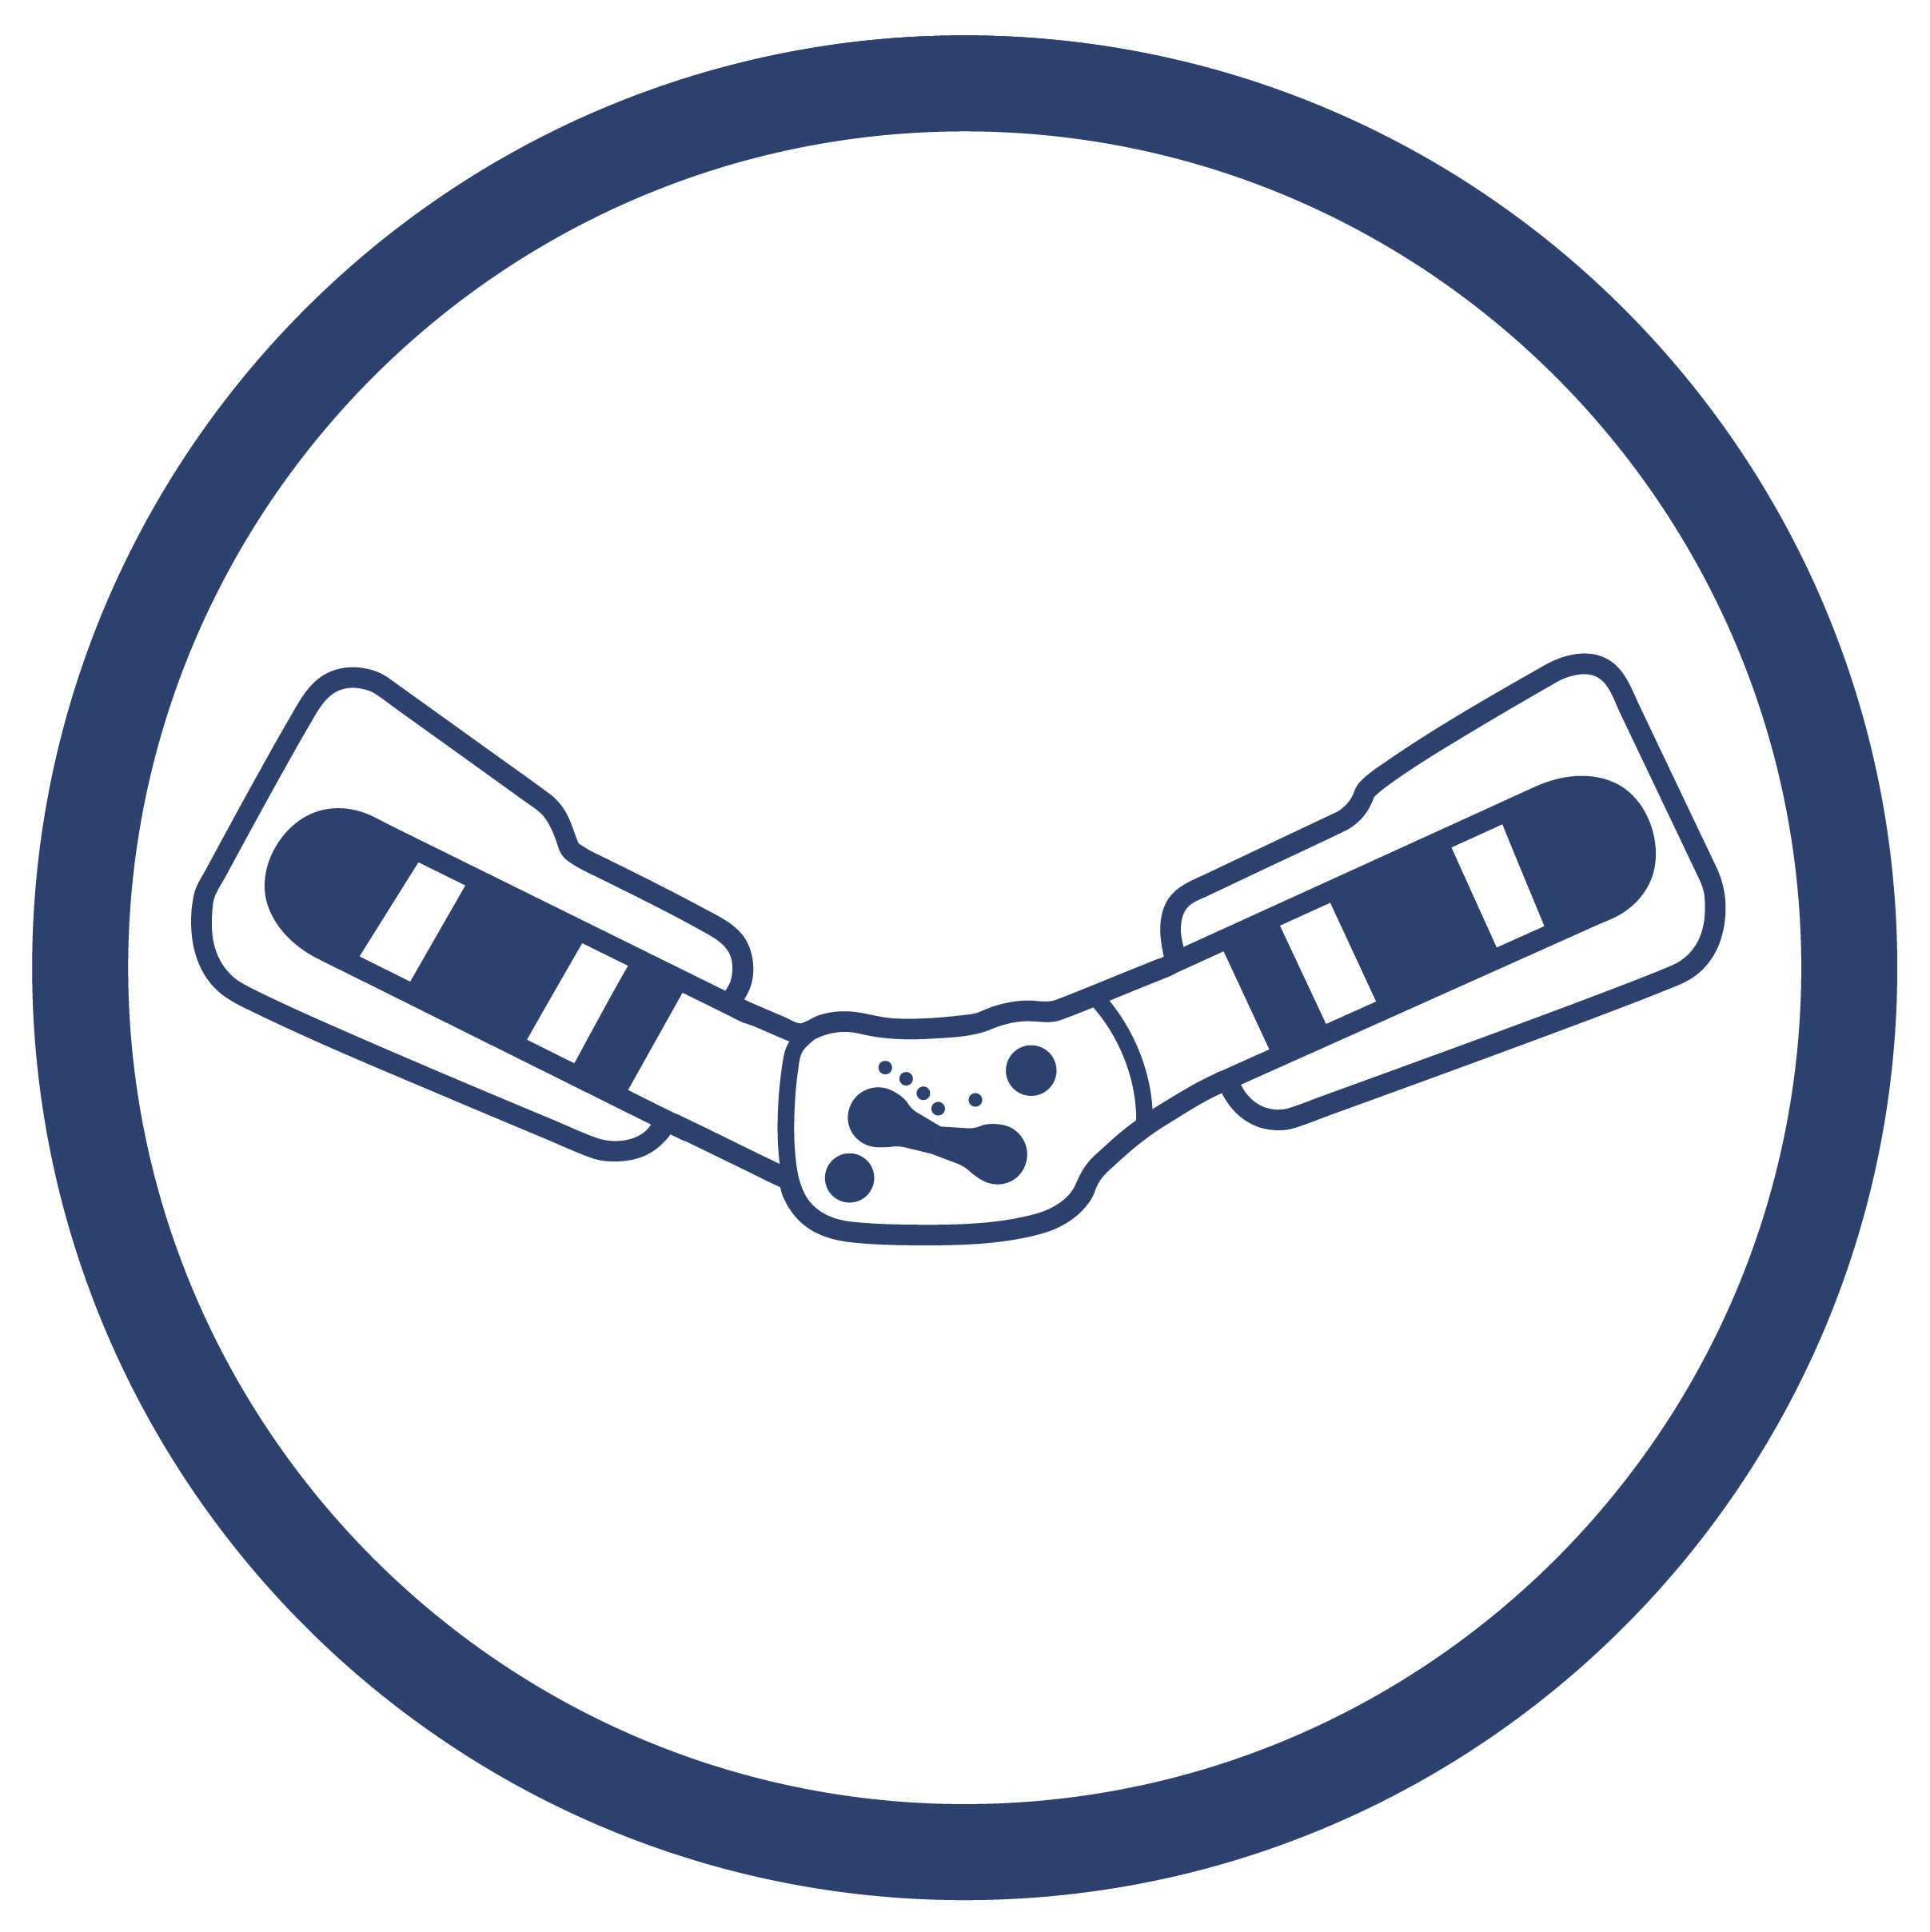

SZYNY 2RA PRECISION PRO

Szyny 2RA Precision Pro to dwuosiowe szyny anatomiczne, które podczas zginania dokładnie odzwierciedlają ruch występujący w stawie kolanowym, przez co w czasie pracy nie zmieniają swojej pozycji względem osi stawu kolanowego. Innowacyjny zawias szyn z technologią ROLL-BACK zapewnia anatomiczne odzwierciedlenie ruchu kolana. Takie rozwiązanie pozwala na wspiercie kolana w trakcie jego zgięcia i wyprostu, ale także utrzymanie stałego kontaktu powierzchni stawowych uda i podudzia, co umożliwia zachowanie naturalnych ruchów rotacyjnych stawu oraz wspiera kolano w każdym fizjologicznym zakresie.

Szyny 2RA Precision Pro to dwuosiowe szyny anatomiczne, które podczas zginania dokładnie odzwierciedlają ruch występujący w stawie kolanowym, przez co w czasie pracy nie zmieniają swojej pozycji względem osi stawu kolanowego. Innowacyjny zawias szyn z technologią ROLL-BACK zapewnia anatomiczne odzwierciedlenie ruchu kolana. Takie rozwiązanie pozwala na wspiercie kolana w trakcie jego zgięcia i wyprostu, ale także utrzymanie stałego kontaktu powierzchni stawowych uda i podudzia, co umożliwia zachowanie naturalnych ruchów rotacyjnych stawu oraz wspiera kolano w każdym fizjologicznym zakresie.

Wykonane są z wysokiej jakości stopu aluminium pokrytego na gorąco trwałą powłoką proszkową, co powoduje że są one obojętne na działanie potu użytkownika i zawartej w nim soli. Szyny anatomiczne posiadają blokadę przeciwprzeprostną, blokadę kąta zgięcia w 10, 30, 40, 60, 75 i 90 stopni oraz ograniczenie wyprostu do 10, 20, 30 i 40 stopni. Istnieje również możliwość całkowitego unieruchomienia kolana w pełnym fizjologicznym wyproście.

Regulacja ta realizowana jest za pomocą specjalnych wkrętów – do każdego wyrobu dodawany jest odpowiedni klucz imbusowy niezbędny do wykonania tej czynności. Sposób regulacji kąta zgięcia, zabezpiecza przed niepożądanym regulowaniem zegara przez osoby nieupoważnione.